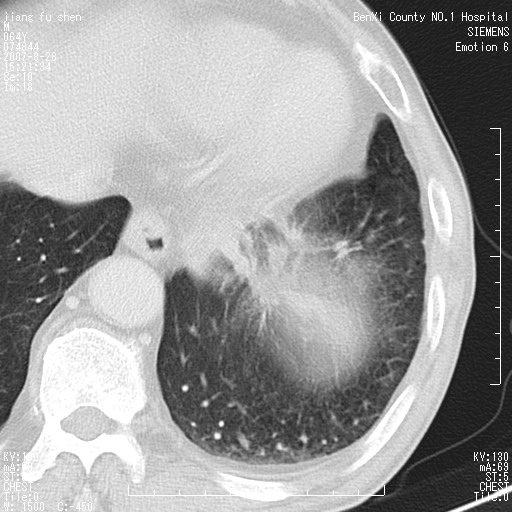

男、64、咳嗽、发烧一周、左肺呼吸音稍弱。既往肺结核,右手结核。

本次扫描患者未带原片,左肺下叶发现病灶。左肺上叶空洞,5组淋巴结肿大,1cm左右。

病灶边缘可见多量较长棘影及纤维条索状影,除外病灶边缘较光整,病灶有分叶表现,但多表现为较浅分叶,且向周围伸出之叶多呈尖角改变,且边缘较光整,病灶增强呈中度延时增强,且早期及中期仅轻度增强,结合患者病史,多考虑继发型肺结核,炎性增殖灶形成,不除外肺癌

左下叶支气管变窄,管腔光滑。软组织形状不规侧,分叶呈角形。结合病史考虑结核可能性大。肺癌不除。